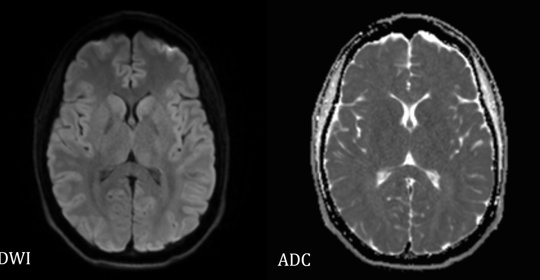

末梢神經病變:診斷方法與涉及科室

神經根傷害:症狀、原因及治療

神經根傷害:症狀、原因及就醫

神經根傷害:診斷方式與治療方法

神經根傷害:原因、症狀與治療

多發性神經炎:臨床表現與診斷